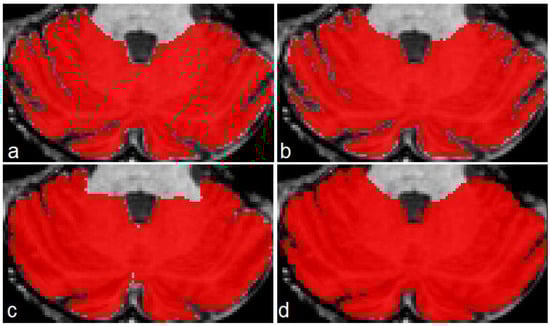

The three models (see Table 1) were tested on five unseen magnetic resonance images. The test subset contained one healthy control (subject 1), two presymptomatic carriers (subjects 2 and 4), and two SCA2 patients (subjects 3 and 5). Figure 4 shows a comparison between the original masks and the segmentations produced by M1, M2 and M3. It can be appreciated the similarity between original and segmented images. Some errors remain, mainly in the contour of segmented masks; those errors will be covered in next investigations. Table 3 shows the result of the evaluations on model M1, segmenting cerebellar fissures only.

Produced segmentations have relatively good scores. Mean DSC and OC are 0.854 and 0.898, respectively. All SP are above 0.99, which means an optimal recognition of background voxels. Low SN values represent some errors in the voxels belonging to cerebellar fissures, mainly in the MRI belonging to the healthy control (0.73, the minimum SN value). It seems that the best behavior was obtained for subject 3, one of the SCA2 patients in our dataset. Note that segmenting cerebellar fissures is a difficult task and, as such, characteristics change greatly between different people. Furthermore, no postprocessing was applied to the results of model M1. Figure 4d shows an example of the outputs produced by our model, compared against the ground truth mask in Figure 4a.

Table 4 shows the evaluation results for model M2 (segmentation of cerebellum tissue with its fissures). As observed, results for this model were much better than the previous one. This is a logical result, considering that segmenting a single, larger structure, which is always located in the same place on MRI, should be easier than segmenting smaller regions with many position changes. The best scores were achieved for the subject 4 MRI, producing better segmentations. The mean values for DSC and OC are 0.973 and 0.987, respectively. SP, SN and AUC are all above 0.98, which means a good background and foreground voxel classification. Figure 4e displays an example output from this model.

Table 5 shows the results for the model segmenting the whole cerebellum (M3). As in Table 4, all scores are above 0.95, which gives the idea of a high precision in the segmentation results. Mean DSC and OC are 0.969 and 0.982, respectively. As in evaluation for model M2, SP, SN and AUC are above 0.98, which means a high-quality segmentation. In a general way, the segmentations obtained by models M1, M2 and M3 have a good quality. Models M2 and M3 obtained better scores than M1.

Figure 4. Masks and predictions for an MRI belonging to one of the SCA2 patients in the test subset. The top row shows the original masks, obtained with the procedure described in Section 2.2, and the bottom row displays the segmentations produced by our models. Cerebellar fissures in (a,d), cerebellum tissue with fissures in (b,e), and whole cerebellum without any fissure in (c,f).